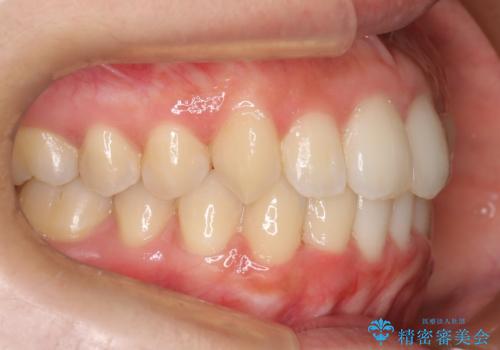

見た目、嚙み合わせ及び、治療期間や施術内容に大変ご満足いただきました。